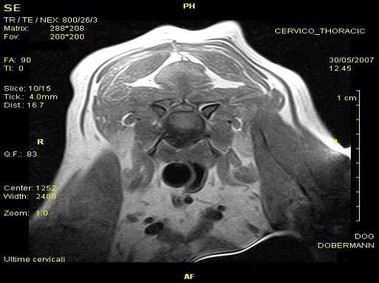

В настоящее время МРТ является наиболее предпочтительным методом визуализации любых мягких тканей, особенно для визуализации травм и патологий центральной нервной системы и суставов. Особенности Vet-MR позволяют использовать данный метод визуализации также в сфере ветеринарии.

Vet-MR специально разработана для визуализации небольших животных и является результатом внимания к деталям при разработке магнита, катушки и электронных компонентов, обеспечивая высокое качество экономически эффективной и простой в использовании МРТ в сфере ветеринарии.

- Высокое качество изображения